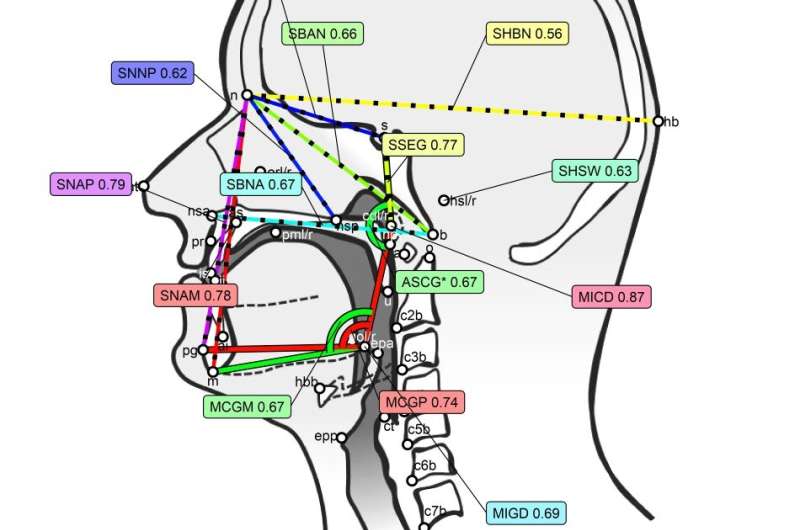

To measure aspects of the vocal tract which are not visible externally, the researchers analyzed 3D structural magnetic resonance imaging (MRI), which capture the anatomical features of both soft and rigid structures of the vocal tract.

One innovative aspect of the methodology of this study is that the analysis of these images was performed by two independent researchers, who first trained in a rigorously defined protocol based on the anthropological and phonetic literature. Following this protocol, they marked, during six months of intensive work, the 3D images to identify clearly defined anatomical structures and to describe curves and surfaces. From these marks, they obtained a set of measurements, such as distances, angles, curvatures, proportions, etc., to capture the dimensions and shape of vocal tract structures and their inter-relationships.

Then, these data were analyzed by genetic structural equation models, allowing the estimation of the contribution of genes to these structures, controlling for potential confounding factors in the data such as the sex, the age or the intercranial volume of the participants, and capitalizing on the information provided by the two researchers who scored all data.

The results provide new evidence on the relative contributions of genetic and environmental factors, sometimes initially surprising for the researchers. Among these were “the position of the larynx, which seems to be under a strong genetic influence, while several bony components, such as the dental arches and hard palate, have low heritability,” notes Scott Moisik, from the Nanyang Technological University. Earlier studies indicated that they seem to change shape in response to the effects of dental treatments, type of diet and even thumb sucking when you are a toddler.

However, “other bony structures such as the nasal cavity and jaw appear to be quite resistant to such environmental influences,” adds Moisik. These results show that genetics matter but not in a uniform way, “to various degrees and at various places of the vocal tract, and it means that it is worth looking for the actual genes involved. But also that genetics is not a ‘jealous master’ that controls everything, which means that we can start looking for the mechanisms through which biology, environment and culture interact.”